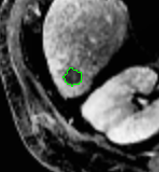

We argue that the sub-optimal paradigm of processing different abstractions within a single CNN pipeline can be remedied through the effective processing of information in a structured manner. Consequently, we devise strategies for disentangling the edge and texture information within a single training pipeline. Figure 2 illustrates how our proposed module, dubbed EG-CNN, can be paired with any existing CNN encoder-decoder to improve segmentation quality near intensity edges. We have applied our EG-CNN to the tasks of brain and liver tumor segmentation in medical images (Figure 3).

(1) Brain MR (2) Liver MR (3) Liver CT (4) Lung CT